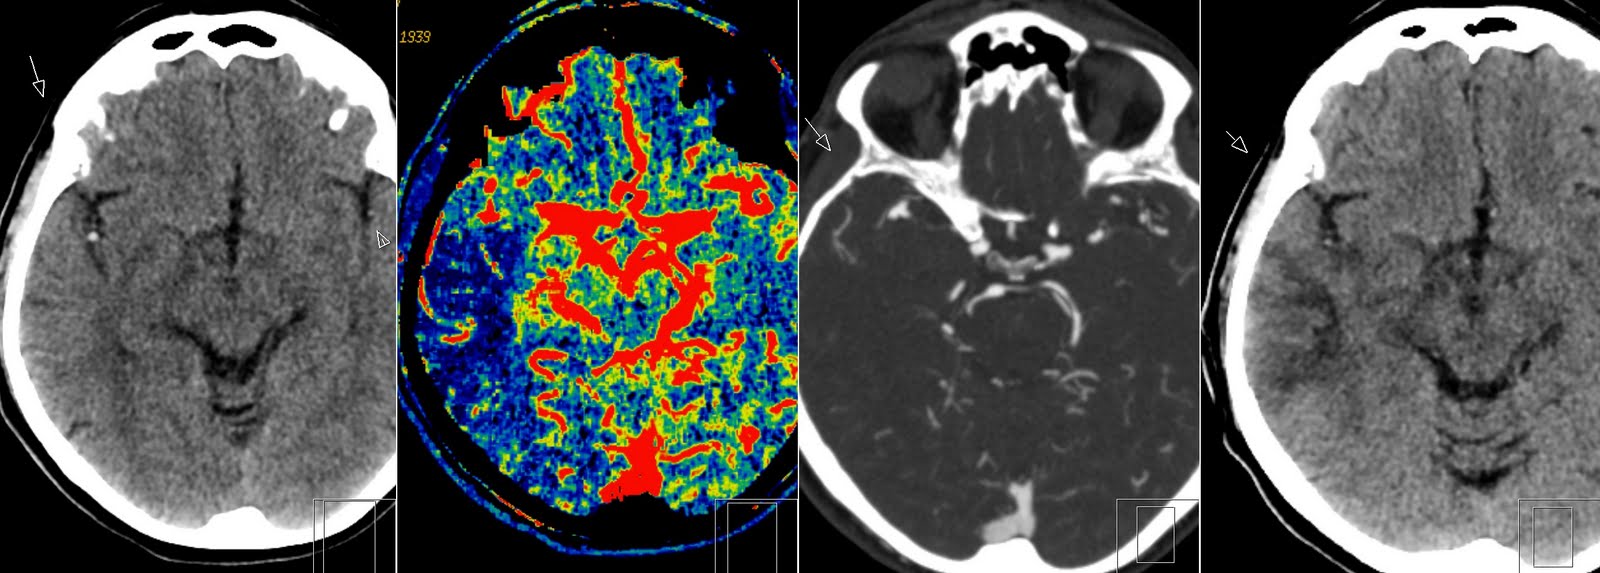

e Axial noncontrast head CT reveals air in the velum interpositum and Velum Interpositum Ct The velum interpositum space is the subarachnoid space between the. the cavum velum interpositum (cvi), considered a normal variant, is a true cistern situated above. the velum interpositum is a triangular space between the two layers of the tela choroidea in the roof of the third ventricle. It is located anteroinferior to the splenium of the corpus. . Velum Interpositum Ct.